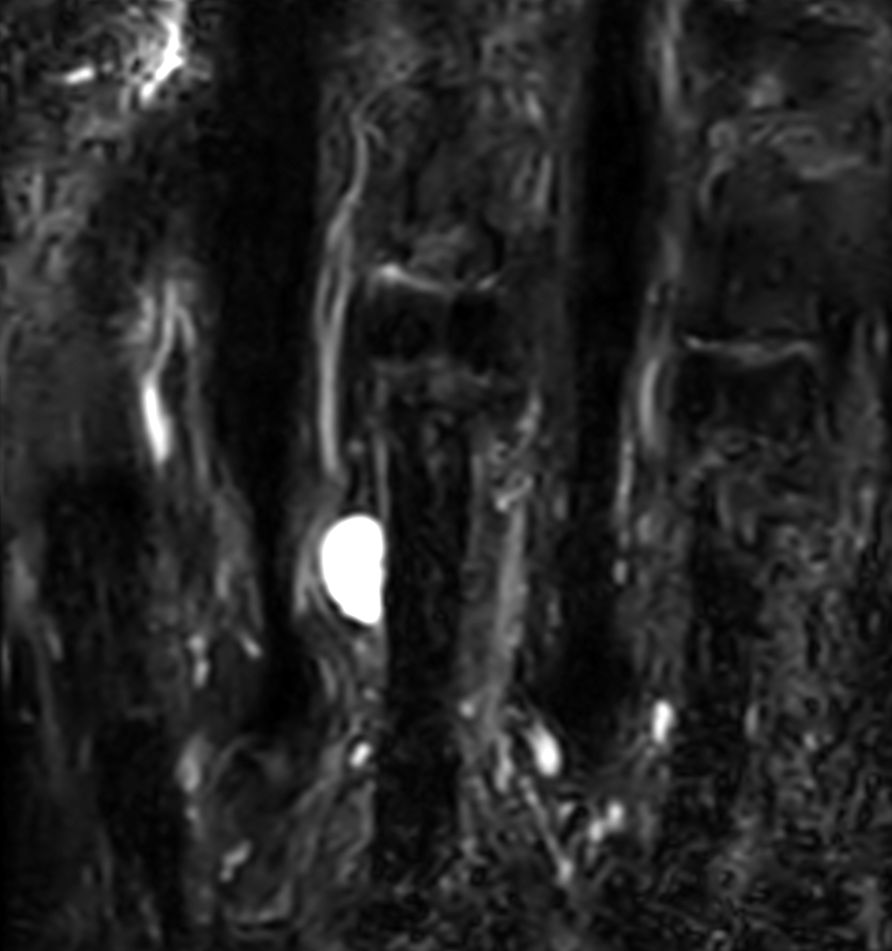

Patient with a ganglion in his finger. dS Microscopy coil set is used, consisting of two 47 mm coils, for small field-of-view imaging with high in-slice spatial resolution and a high signal-to-noise ratio. Compressed SENSE is used in all sequences to shorten the overall exam time for the patient.

Coronal STIR TSECompressed SENSE